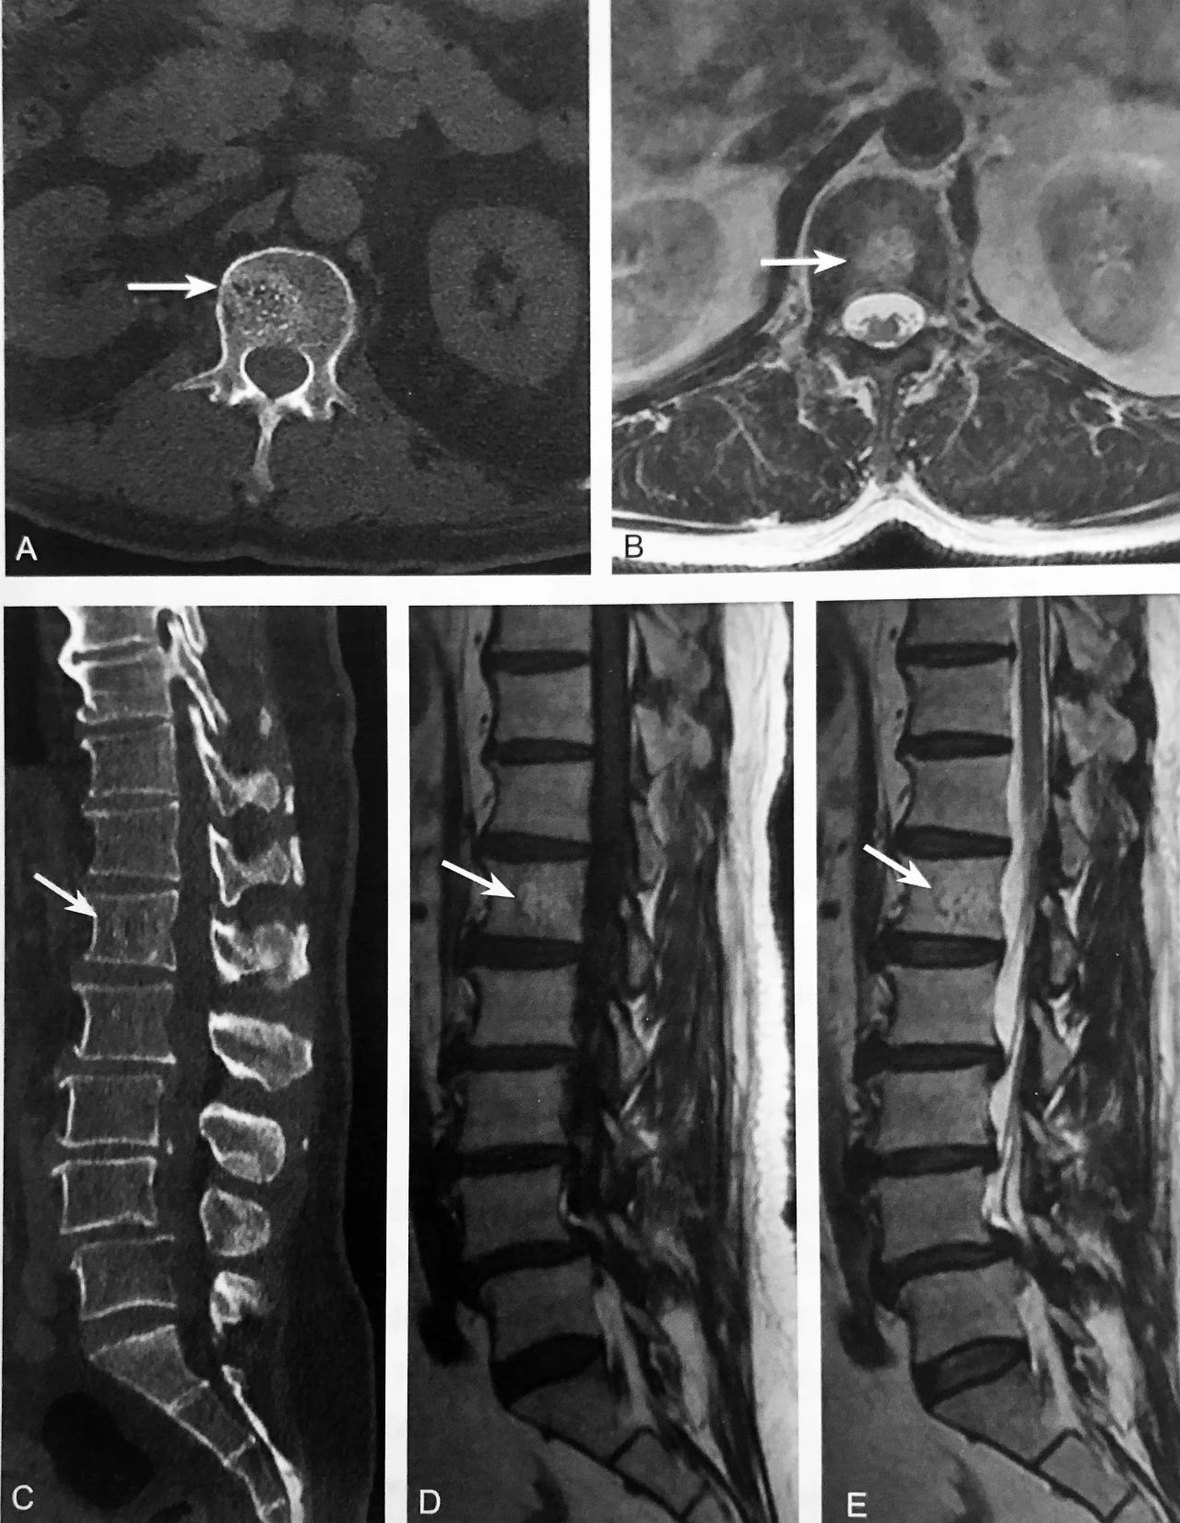

MRI 液 体 征

A~B.L1 椎体良性压缩性骨折,邻近骨髓水肿,T1WI 呈弥漫性低信号,T2WI 呈条带状高信号(箭头),位于 L1 椎体上终板下方;C~D.L1 椎体良性压缩性骨折,邻近骨髓水肿,T1WI 呈弥漫性低信号,T2WI 呈三角形高信号(箭头)

判读要点:

1、在脊柱 MRI 矢状位观察;

2、MRI 液体征常见于压缩椎体上终板下缘或下终板上缘;

3、表现为形状规则或不规则圆点状、线样或三角形,T1WI 呈低信号,T2WI 呈高信号,T2WI STIR 呈明显高信号;4、需与肿瘤侵犯推体所致压缩骨折鉴别。